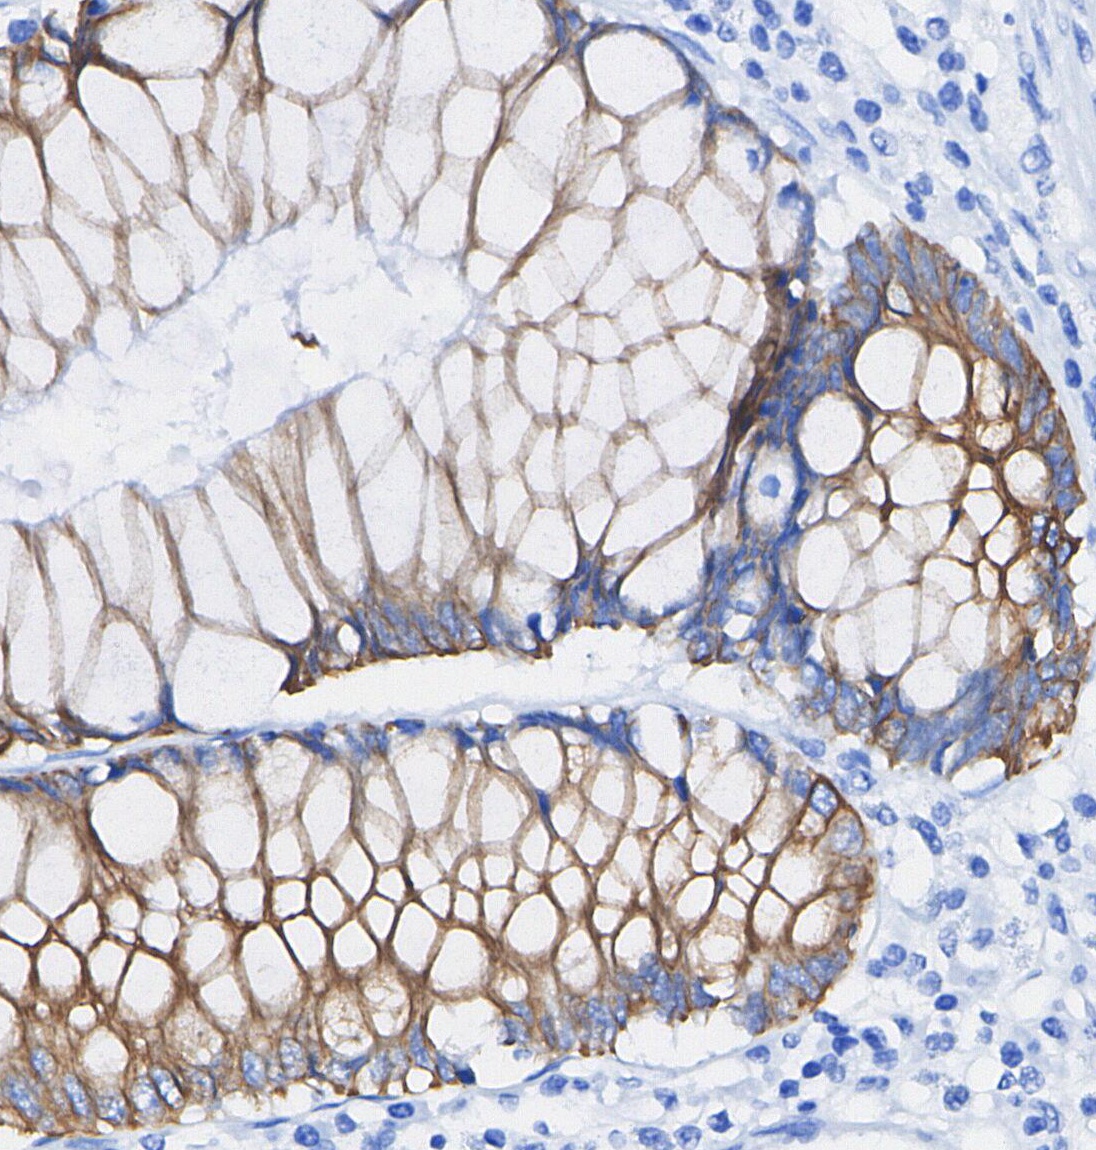

• Immunohistochemical analysis of formalin fixed paraffin embedded human Colorectal cancer tissue with F0482 at 1/100 dilution.